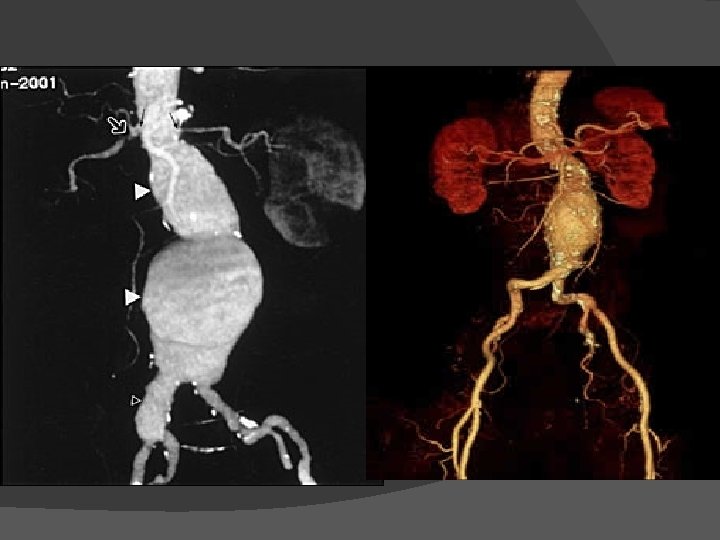

Diagnostic imaging � Abdonimal USG �Non-invasive, inexpensive, free of radiation and contrast free � CT angiogram �More accurate than USG �Relationship of AAA with other vessels �Coexisting mural thrombosis, calcification, occlusive atherosclerosis �Enhance visualization of AAA before EVAR � MRA- Magnetic resonance angiography

EVAR-Preop planning and imaging � To define the anatomy � To determine the feasibility of endovascular repair � To choose the size and configuration of endograft components � CT angiography with 3 -D reconstruction preferred because in 2 D CT- aortic diameter measurements sometimes overestimated if the aorta is angulated and the longitudinal axis is not perpendicular to the imaging plane � MR angiography in setting of renal dysfunction. But MRA fails to depict vessel wall calcification, which has implications for vascular access